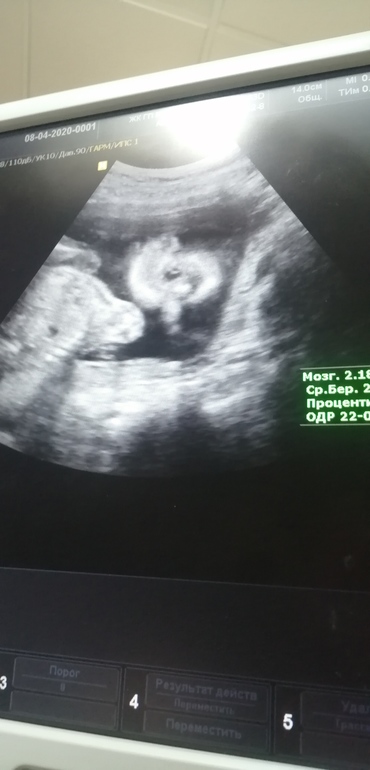

УЗИ,❤️❤️❤️❤️❤️И всё таки у нас девочка🙂🙂🙂

Как часто можно делать УЗИ В 1м триместре? Сходила на первое узи